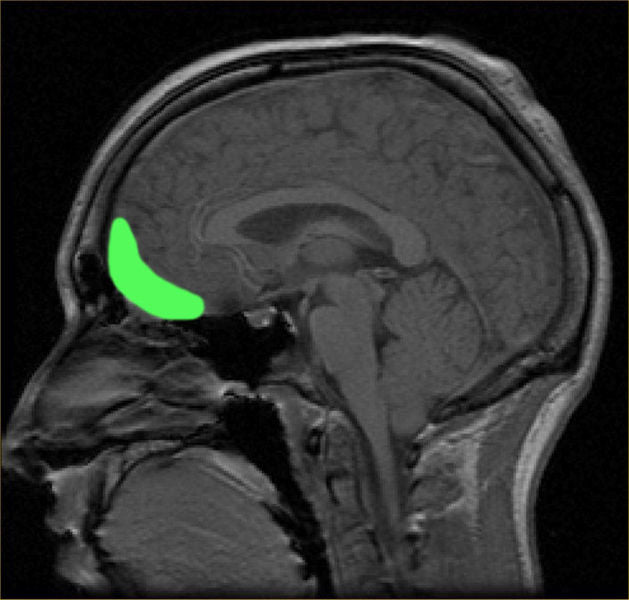

When it comes to sexual pleasure, your brain plays a significant role. The brain releases a cascade of hormones and neurotransmitters during sexual arousal and orgasm, including dopamine, oxytocin, and endorphins. These chemicals are known to influence mood, pleasure, and even cognitive function.